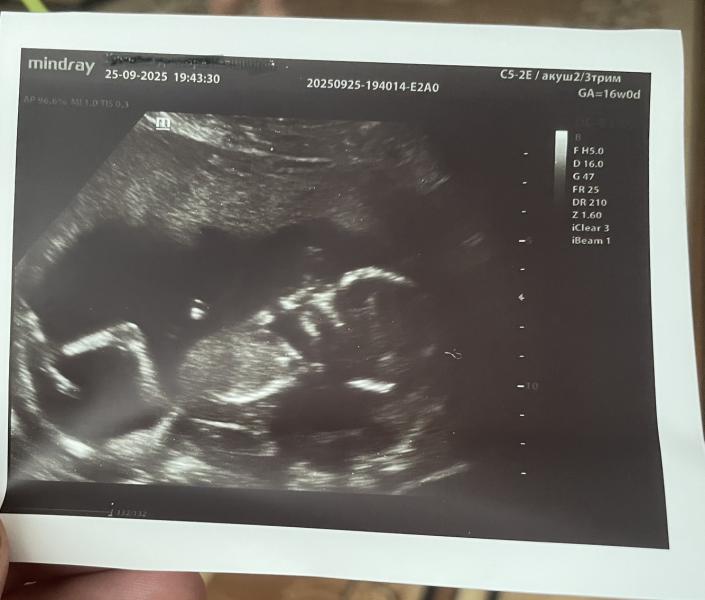

Заветная бумажка: волнительное ожидание и маленький праздник

Заветная бумажка ,так волнительно 🥰Ин ша Аллах ,завтра узнаем 🩷

Решила устроить дочке маленький праздник ,заказала тортик и шарик ☺️💖